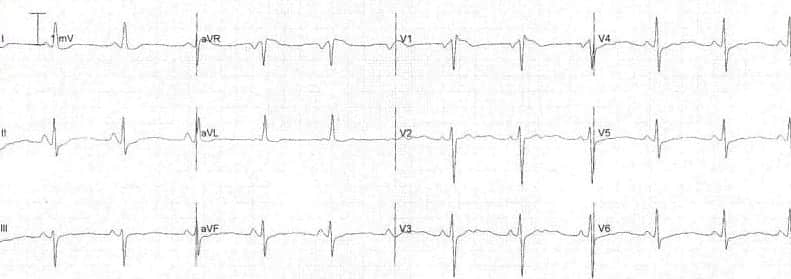

ECG Example – Pathological Q Wave

This ECG demonstrates pathological Q waves in leads V1-V4 (most prominent in V1-V3), due to anterior myocardial infarction.

© Life in the Fast Lane. Licensed under CC BY-NC 4.0